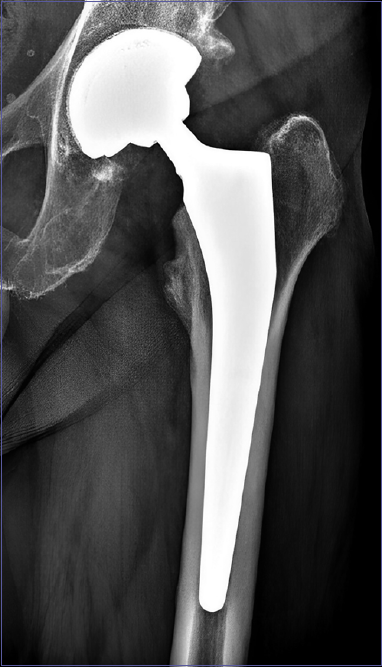

Figure 1.Seventy-five-year-old woman treated with total hip arthroplasty. A) at the post-operative X-ray is possible to see a radiological divergence of the shell line indicative of mispositioning (black arrow); B) at 1 year follow-up the divergence disappeared.

Figure 2.Fifty-eight-year-old man treated with total hip arthroplasty. Radiological divergence of the shell is visible at one-year follow-up. The patient showed no pain in weight-bearing or hip motion.

Figure 3.Sixty-one-year-old woman treated with total hip arthroplasty. The patient showed a progressive increase in the divergence of the shell line until subluxation of the implant head, with pain and a squeaking noise during motion. She eventually underwent revision surgery.

Three patients had radiographic evidence of liner mispositioning, two cases in the Permedica group and one in the Stryker MDM group®. In one of the two patients, radiological divergence of the shell line indicative of mispositioning, clearly identified on post-operative CT and radiography, disappeared at one-year follow-up, while in the other patient the radiographic divergence was observed at all subsequent follow-ups even if still in the short term (48 months). Both patients had excellent clinical evaluation (mean HHS at month 6: 89.9 ± 2.3; mean HHS at one year 95.6 ± 1.6) (Figs. 1 and 2). The third patient, from the Tritanium MDM Stryker group®, had an unfavorable evolution with a progressive increase of the divergence of the shell line associated with a painful noise The patient therefore underwent revision surgery and after the operation the HHS had a remarkable improvement (Fig. 3).